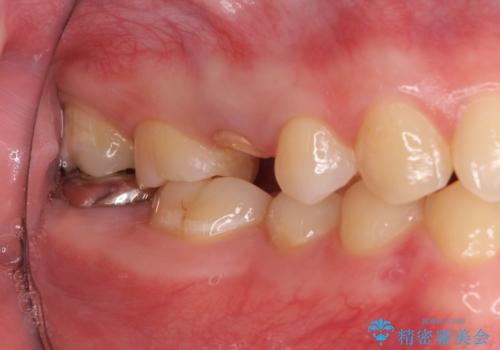

右上の被せものを除去したところ、中で歯が割れていたため、部分矯正で引っ張り出すことになりました。

・両どなりの歯に一時的にワイヤーを接着します。